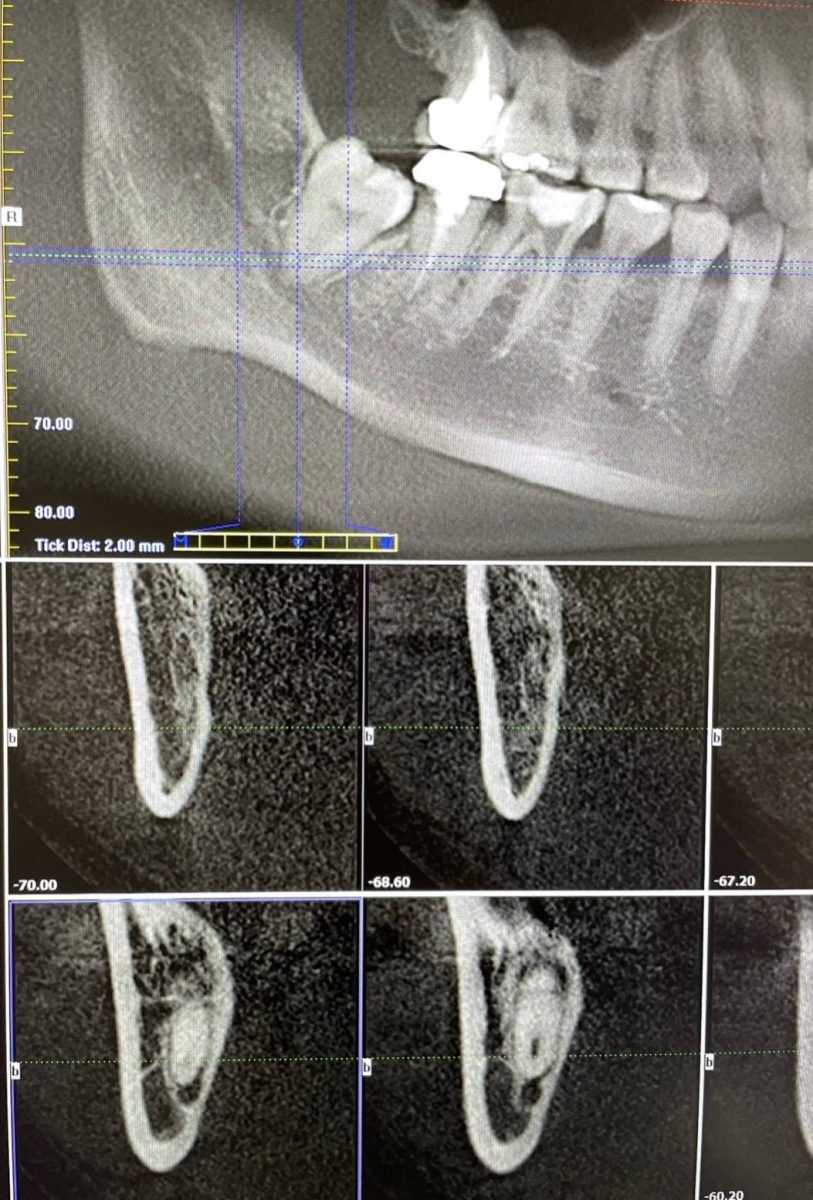

徐偉軒安排TCI鎮靜舒眠麻醉,以微創手術不影響下齒槽神經的方式,安全替患者拔除智齒。圖:聖保祿醫院提供

聖保祿醫院提到,原本非常害怕看牙醫的王小姐,面對治療更是恐懼,所幸徐偉軒安排TCI鎮靜舒眠麻醉,以微創手術不影響下齒槽神經的方式,安全拔除右下智齒,術後搭配高壓氧治療並服用維生素B群。手術後觀察1週,下巴麻木情形改善很多,追蹤2週後,下巴很多知覺都逐漸回復,臨床偵測麻木疼痛的區域,由原本大約一個巴掌大範圍,已縮減到一元銅板大小,不會疼痛,並逐漸康復,病患的生活品質獲得大幅提升。